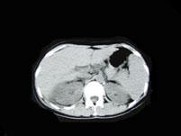

- 多项选择题女,33岁, 右肋腹痛7天,尿检可见大量的脓细胞, CT平扫+增强如图所示,下列说法正确的是 ( )

A、右肾体积增大,其内可见类圆形低密度病灶

B、增强扫描可见该病灶不均匀强化,其内有无强化的坏死灶

C、右肾病灶边界模糊不清

D、考虑为右肾囊肿合并感染

E、考虑为右肾脓肿